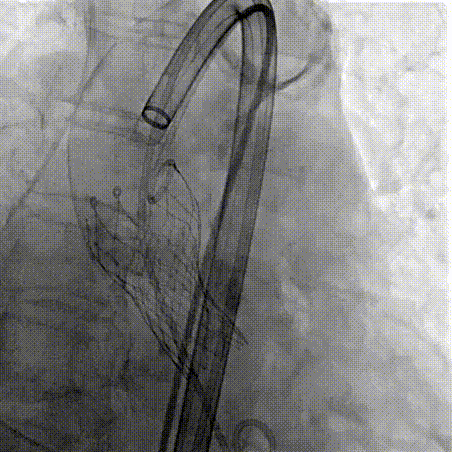

Step 9.CuspOverlap体位验证缘对缘对齐,挂钩位于最右方,基本避开冠脉开口

Step 10.验证器械同轴性,完全同轴